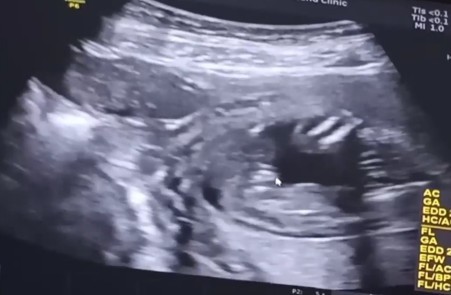

รูปนี้ซาวตอน 13 week ป้าหมอบอกว่าน่าจะผู้หญิง แม่ๆช่วยดูหน่อย จะหญิงจริงๆมั้ยคะ แม่ว่าจะรอดูซาวรอบหน้าอีกที ตื่นเต้นค่ะ😊🥰

ซาวด์มาล่าสุด 19w คุณหมอแจ้งว่าได้น้องผู้หญิงค่ะ 🥰 ดูจากรูปน่าจะได้น้องผู้หญิงเหมือนกันนะคะแม่

น่าจะผู้หญิงนะคะ เพราะภาพอัลตร้าซาวด์ คล้ายของเราค่ะ

นี้คุณหมอก็บอกผู้หญิงช่วยดูหน่อยคะ ดูไม่ออกเลย